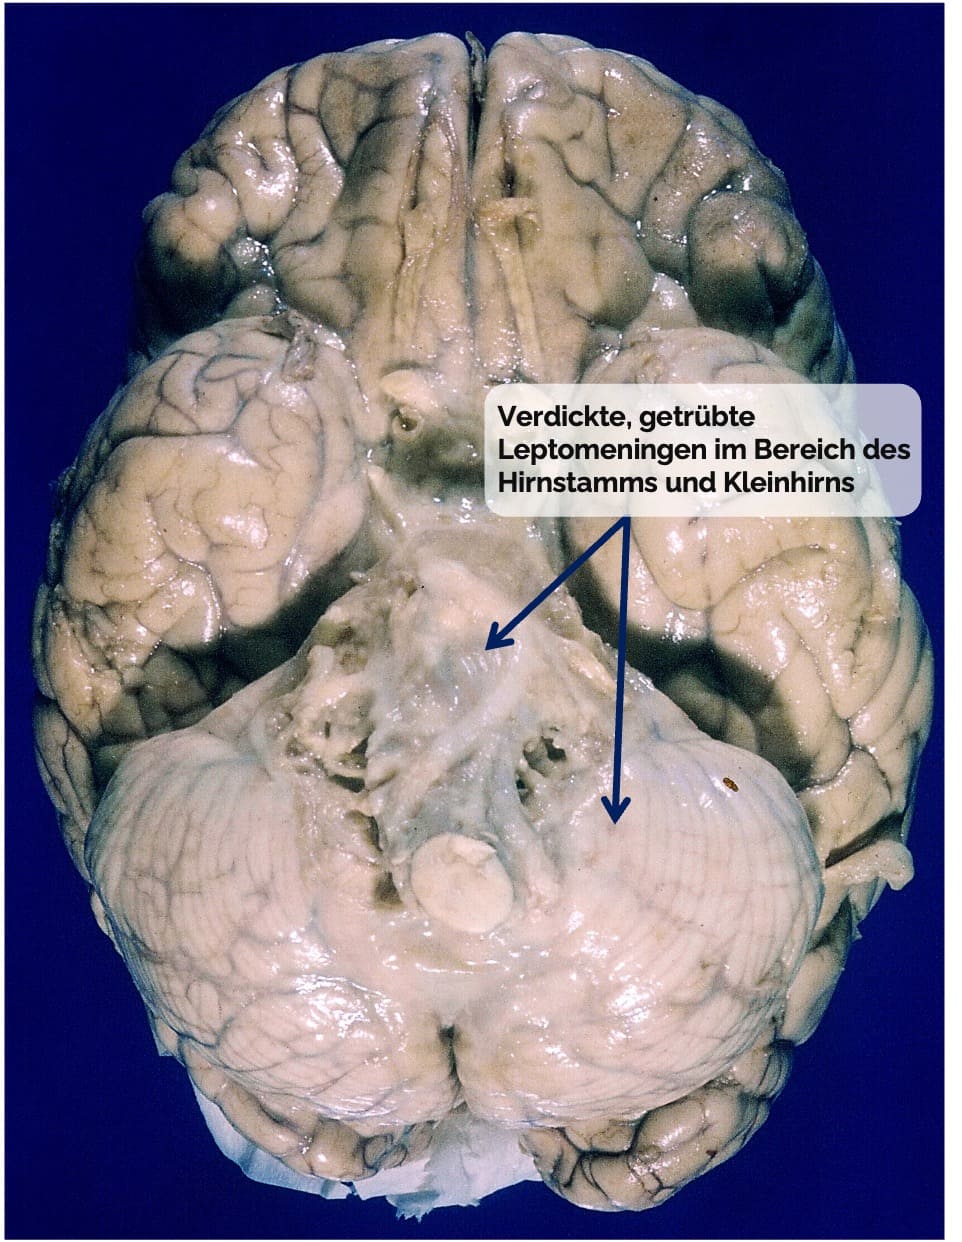

Makroskopie:

Hyperämie, Verdickung und Trübung der Leptomeningen → dadurch kortikale Windungen nicht mehr erkennbar

Eitriges, grünliches Exsudat im Subarachnoidalraum, insbesondere fronto-parietal lokalisiert (→ sog. Haubenmeningitis)

Beispiel: Tuberkulöse Meningitis

Lokalisation: Vorzugsweise an der Hirnbasis (→ basale Meningitis)

Basale Meningitis mit gelatinöser Trübung und Spinngewebsgerinnseln im Bereich der Zisternen